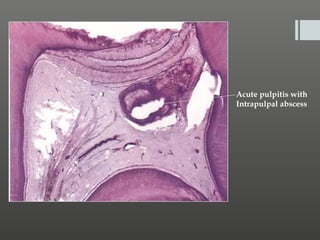

Histopathology:

 T post capillary venules becomes congested,

he

T

hese attract the polymorph nuclear leukocytes, by

chemotaxis and start an acute inflammatory reaction

 T inflammatory reaction produces micro-abscesses(acute

his

pulpitis).

 Microscopically one sees area of abscess and a zone of

necrotic tissue, with microorganisms present in the late

carious state, along with lymphocytes, plasma cells and

 No microorganisms are found in the center of the

abscess because of the phagocytic activity of the

polymorph nuclear leukocytes.

Acute pulpitis with

Intrapulpal abscess